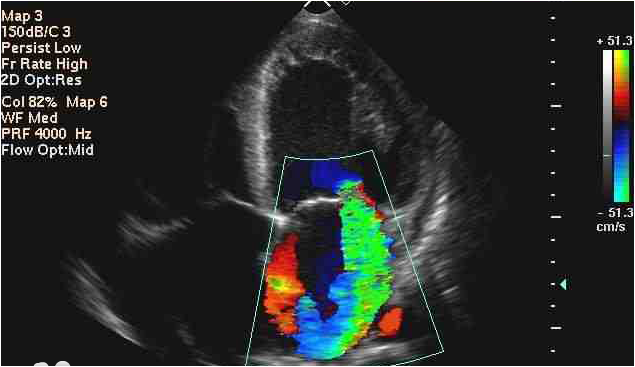

- ECOCARDIOGRAFÍA: Nos mostrará la morfología y el funcionamiento del músculo y las válvulas cardíacas para descartar enfermedades que supongan un riesgo para la práctica del deporte. Prueba muy recomendable en un estudio inicial de cualquier deportista